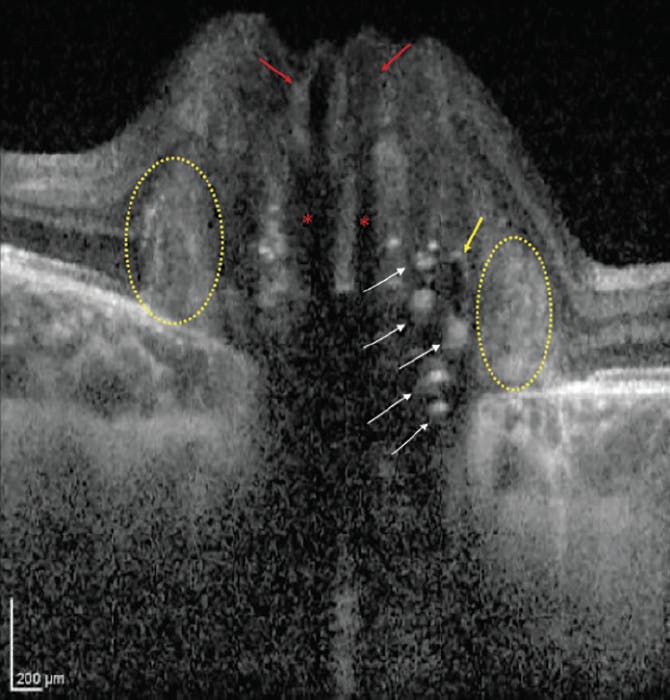

The ODDS Consortium also identified other findings on OCT that can be mistaken for ODD. Blood vessels caught in cross-section can appear as small circular objects with trilayer reflectivity—typically with a hyperreflective wall, an inner hyporeflective ring, and a hypo- or isoreflective core (Figure). However, there will be significant shadowing of the underlying layers, which is not seen with ODD. As arterioles and venules travel together out of the optic nerve head, the two lumina are often seen adjacent to each other in a figure-eight configuration—although this may not be evident if vessels are imaged in an oblique or longitudinal fashion. When in doubt, scrolling through the OCT raster scan can help distinguish between the tubular course of blood vessels and a more discrete ODD.

<p>Figure. This EDI SD-OCT of an optic disc reveals several features. ODD (yellow arrow) usually have a hyporeflective core and hyperreflective margin. They are found above the lamina cribrosa. Conglomerates of hyperreflectivity may also represent early disc drusen (white arrows). Blood vessels (red arrows) can be caught in cross-section and often present with trilaminar reflectivity. Arterioles and venules frequently travel together in a figure-eight formation. Vessels are distinguished from ODD by posterior shadowing (red asterisks). PHOMS (yellow circles) are not ODD and instead may represent bulging axons.</p>

Figure. This EDI SD-OCT of an optic disc reveals several features. ODD (yellow arrow) usually have a hyporeflective core and hyperreflective margin. They are found above the lamina cribrosa. Conglomerates of hyperreflectivity may also represent early disc drusen (white arrows). Blood vessels (red arrows) can be caught in cross-section and often present with trilaminar reflectivity. Arterioles and venules frequently travel together in a figure-eight formation. Vessels are distinguished from ODD by posterior shadowing (red asterisks). PHOMS (yellow circles) are not ODD and instead may represent bulging axons.

Patients with ODD also commonly exhibit peripapillary hyperreflective ovoid mass-like structures (PHOMS) on OCT. In the past, researchers debated whether these represented variants of ODD.5-7 However, PHOMS are hyperreflective, not hyporeflective, and lack sharp margins. They are also found external to or surrounding the disc. Unlike ODD, they are not visible on ultrasonography or FAF. In addition, OCT detects PHOMS in patients with papilledema without ODD,8 suggesting that they are not specific to pseudopapilledema. The ODDS Consortium suggested that PHOMS correspond with lateral bulging of optic nerve axons into the peripapillary retina and recommended that they be excluded as a criterion for the diagnosis of ODD unless future histopathologic evidence suggests otherwise.5